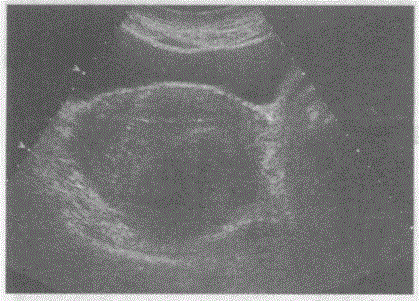

问题 临床资料:女,44岁,自述痛经14年,进行性加重。 超声综合描述:子宫前位,增大,子宫内膜前移,前壁厚度2.5cm,后壁厚度5.3cm,后壁回声明显不均,可见低回声区,边界不清。 超声提示:

选项 A.子宫正常声像图 B.子宫肌瘤 C.子宫内膜息肉 D.子宫腺肌症合并腺肌瘤

答案 D